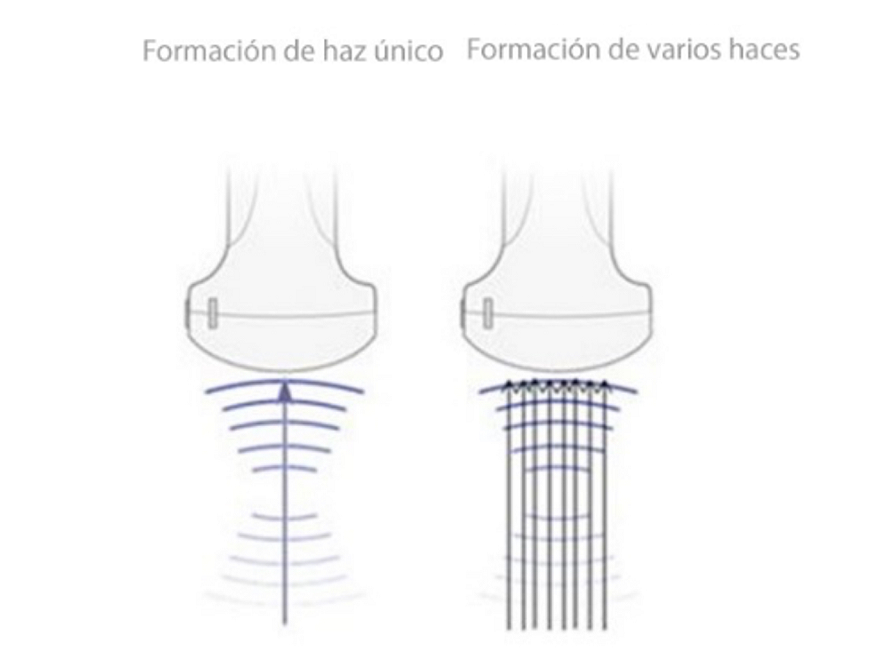

Formación de varios haces

iBeam? (Toma de imágenes de composición espacial)